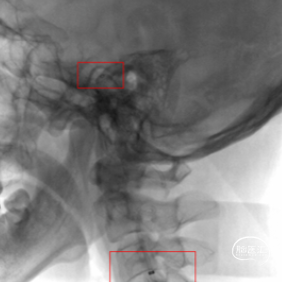

术前造影,BA近端闭塞。

术前造影,LC7次全闭塞。

术前造影,RICA 通过交通动脉向左侧颈内动脉及基底动脉尖代偿供血。